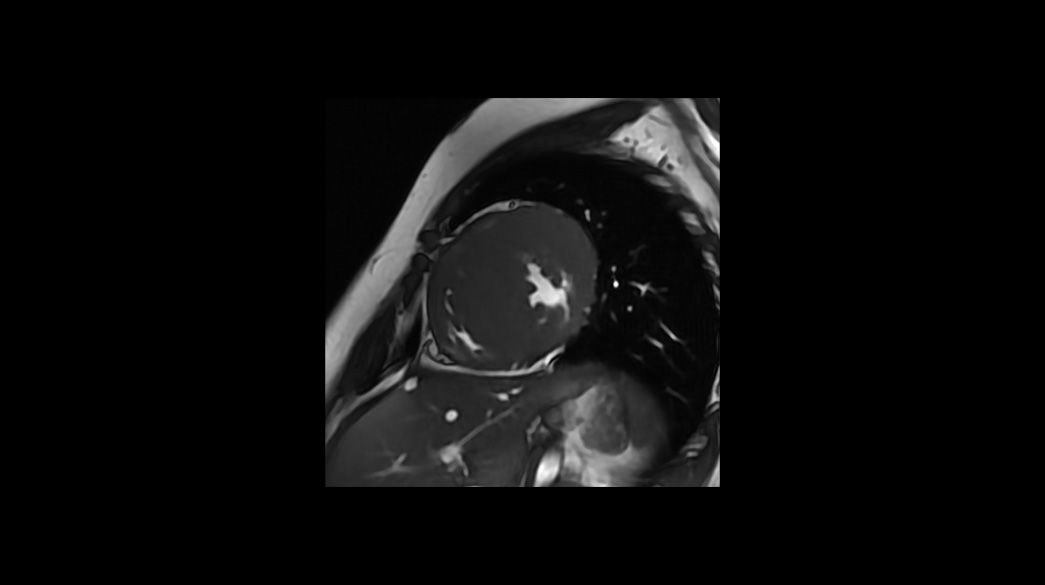

3D-Heart1040-x-585

Read case study